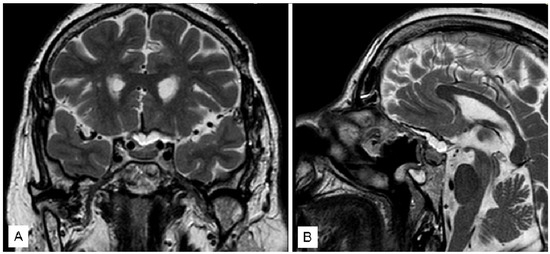

3.1.3. Case 3